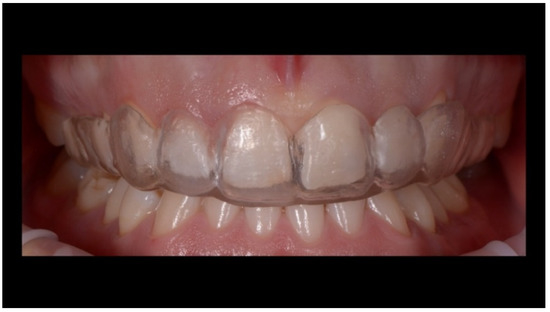

Case Report